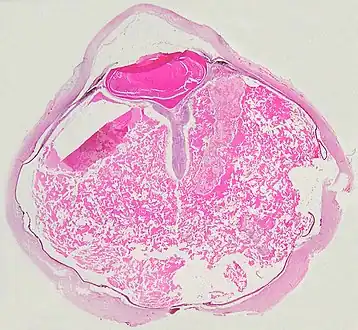

Grossly, retinal detachment and yellowish subretinal exudate containing cholesterol crystals are commonly seen. Microscopically, the wall of retinal vessels may be thickened in some cases, while in other cases the wall may be thinned with irregular dilatation of the lumen.[10] The subretinal exudate consists of cholesterol crystals, macrophages laden with cholesterol and pigment, erythrocytes, and hemosiderin.[11] A granulomatous reaction, induced by the exudate, may be seen with the retina.[12] Portions of the retina may develop gliosis as a response to injury.

A case of Coats' disease, showing total exudative retinal detachment, and subretinal exudate containing cholesterol crystals (H&E)